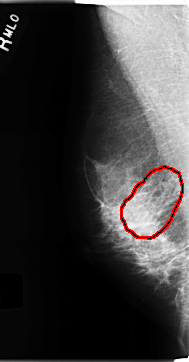

RIGHT_MLO LINES 4704 PIXELS_PER_LINE 2448 BITS_PER_PIXEL 12 RESOLUTION 50 OVERLAY

FILE: C_0198_1.RIGHT_MLO.OVERLAY

TOTAL_ABNORMALITIES 1

ABNORMALITY 1

LESION_TYPE CALCIFICATION TYPE AMORPHOUS DISTRIBUTION SEGMENTAL

ASSESSMENT 4

SUBTLETY 2

PATHOLOGY MALIGNANT

TOTAL_OUTLINES 1

BOUNDARY